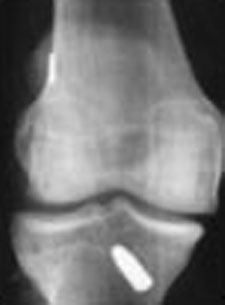

Post-op X-ray